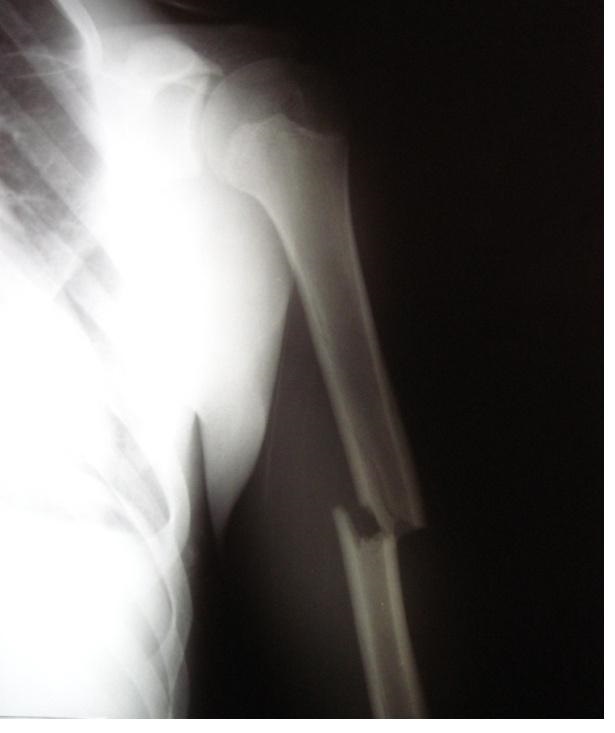

Pytanie 1

Który z nerwów jest najbardziej narażony na uszkodzenie w złamaniu przedstawionym na zdjęciu RTG?